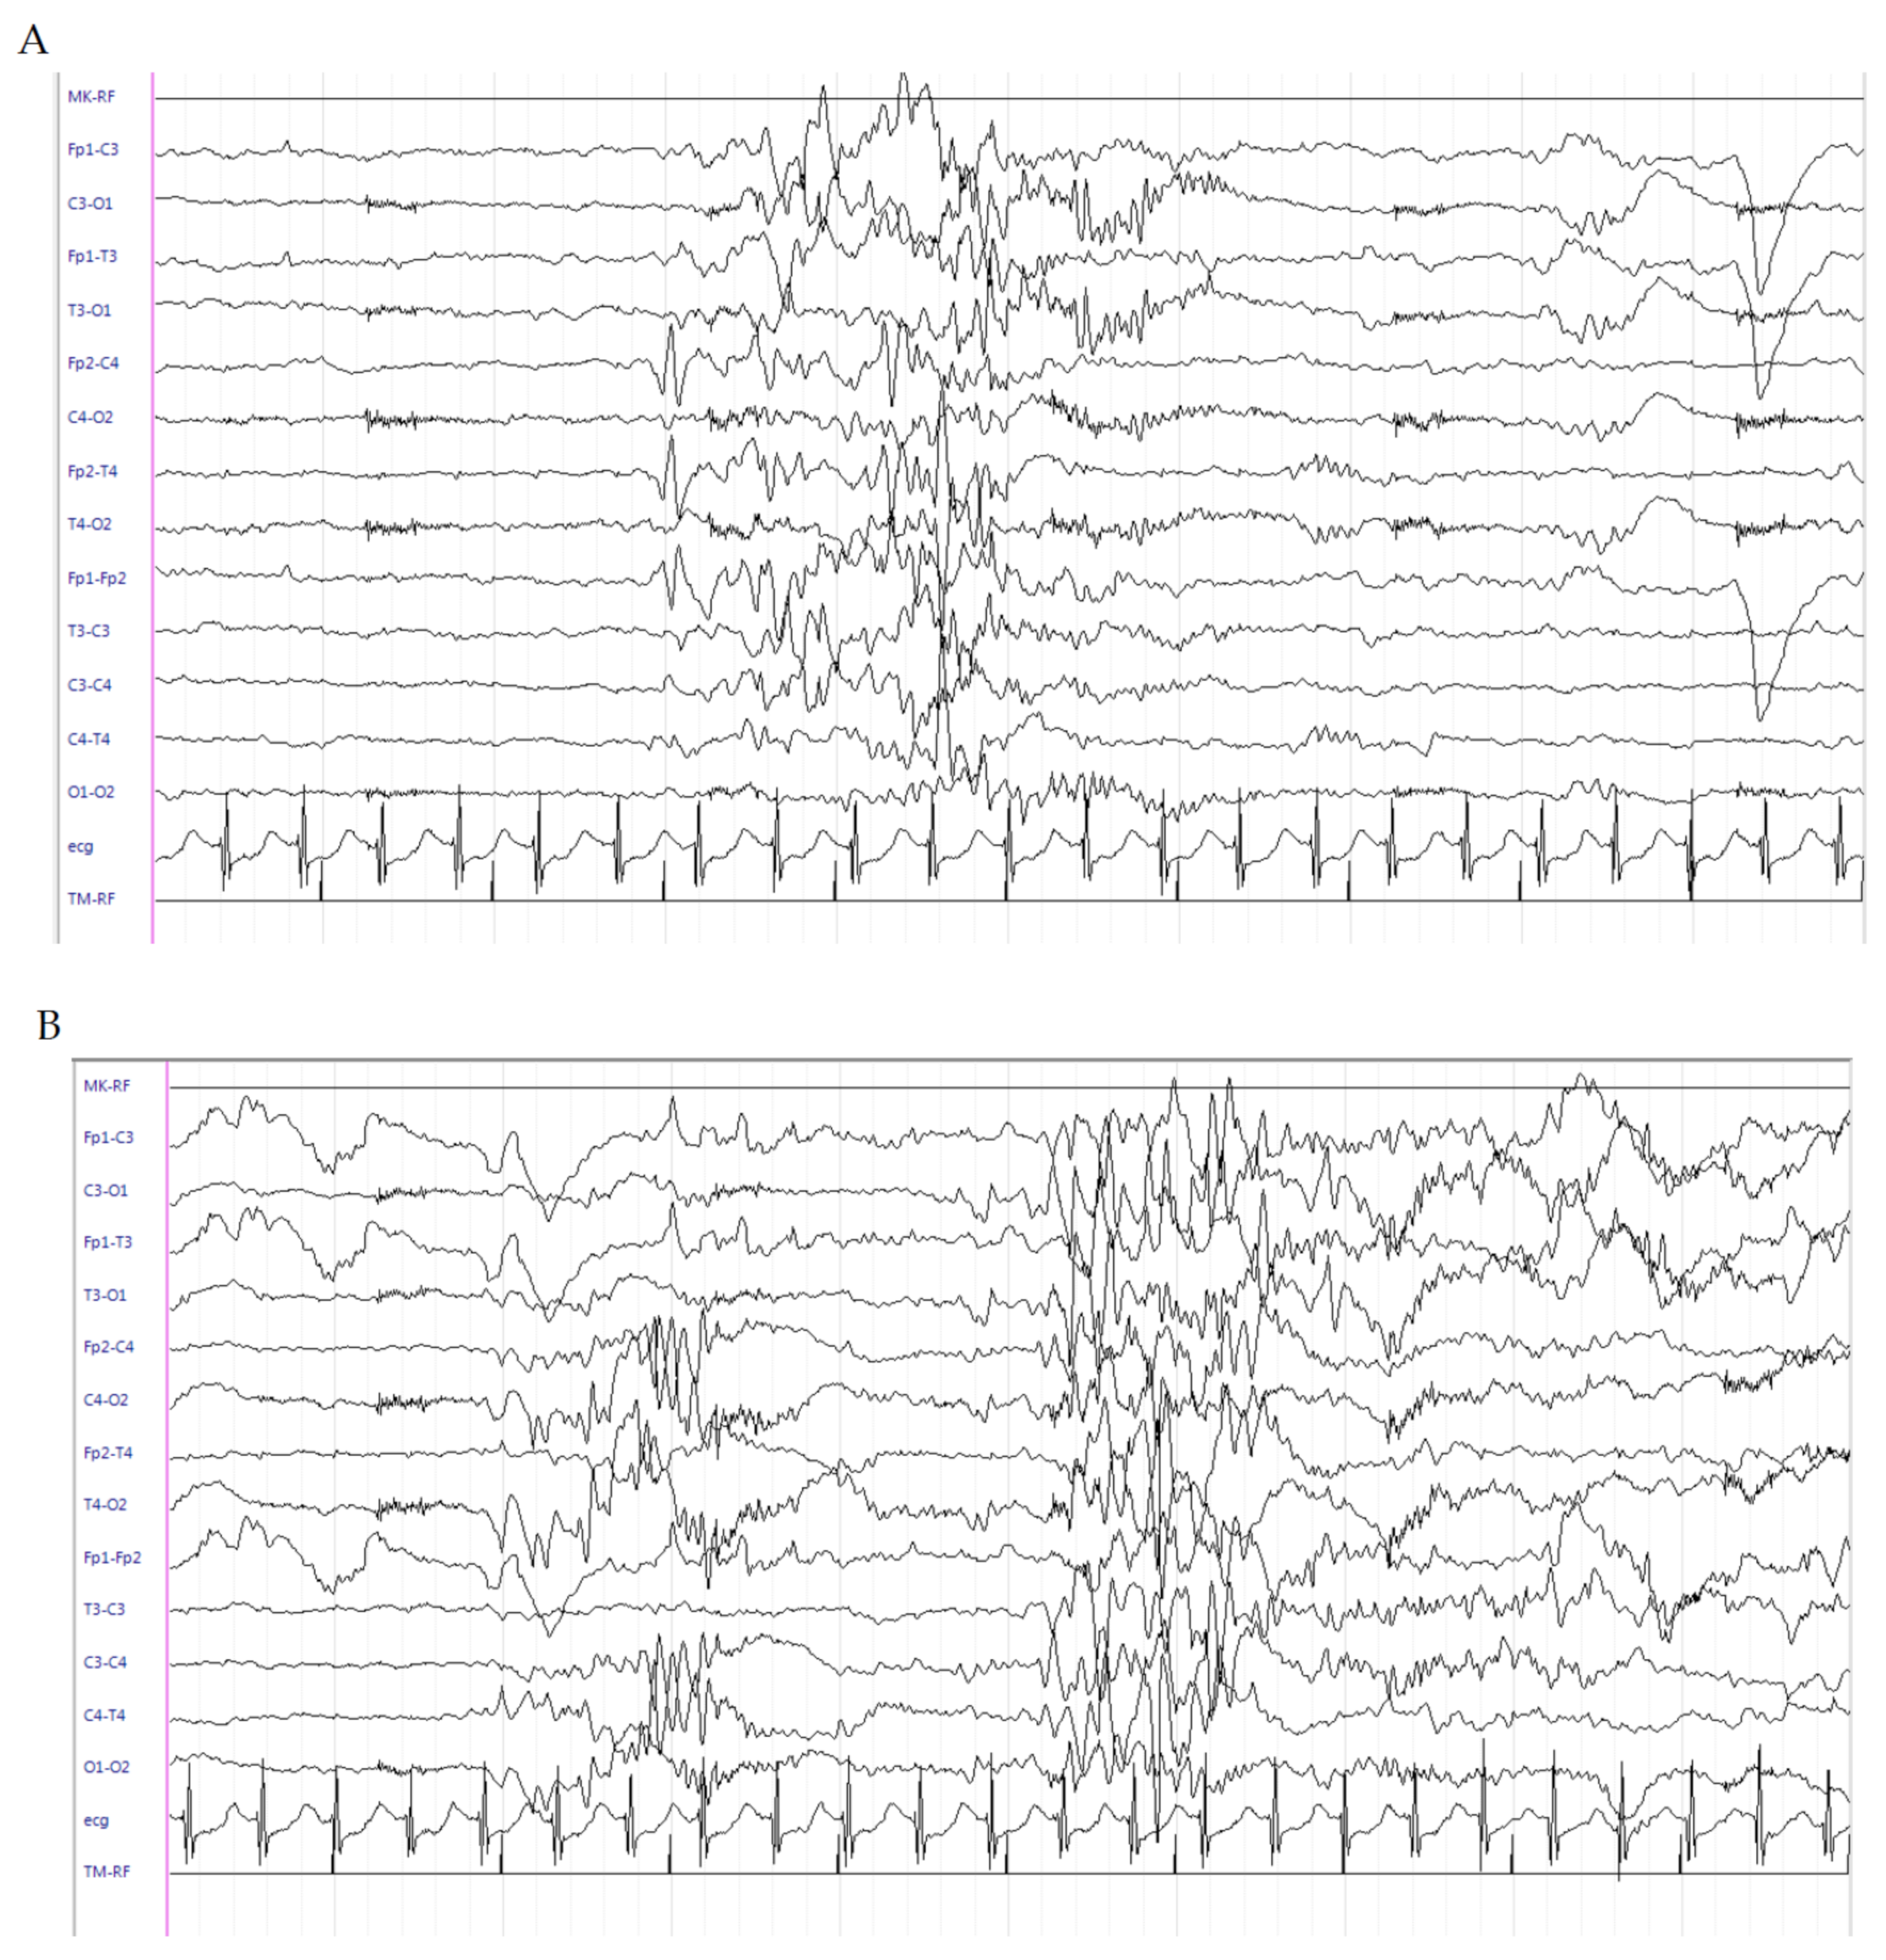

This is a male patient born at 304/7 weeks of gestational age (GA) from an unremarkable pregnancy, by emergency caesarean section (TC) due to metrorrhagia. Apgar score was 3 at 1 min and 7 at 5 min. Birth weight was 2100 g (>97th percentile). He was admitted to the Neonatal Intensive Care Unit (NICU) with immediate start of noninvasive ventilatory support; however, due to worsening of respiratory conditions, he was intubated and treated with surfactant. Seizures occurred at 3 days old and were characterized by clonic jerks at the lower right limb, often spreading to the right hand and to the counter-lateral limbs, recurring at least 1–2 times/h and lasting for about one minute. Sleeping electroencephalogram (EEG) activity showed an interictal pattern characterized by onset of high-voltage delta waves in left frontal regions, suddenly spreading to the counter-lateral homologous regions (Figure 1A) and subsequent generalization, followed by medium–high-voltage delta waves in bilateral centrotemporal regions (Figure 1B). Interictal neurological examination showed severe diffuse hypotonia and extremely poor general movements. Intravenous (IV) levetiracetam (LEV) (40 mg/kg) as a bolus was administered with only a partial reduction of seizures (occurrence once every 1–2 h). LEV was continued with a maintenance dose of 10 mg/kg/dose three times daily. Pyridoxine as a bolus (100 mg/day) was administered. Due to the seizures persisting, PB (20 mg/kg) as a bolus was administered with transient seizure disappearance; however, they relapsed after 3 h. IV infusion with midazolam was started and uptitrated to 2 μg/kg/min with poor results. Sleeping EEGs were serially performed and showed persistence of electric seizures without relevant clinical manifestations. Cranial ultrasound (CUS) scan failed to detect brain abnormalities. Brain MRI scan was performed, showing eccentric venous thrombosis at the superior right sagittal and left transverse sinuses. Low-molecular-weight heparin (LMWH) therapy was started at a dosage of 150 IU/kg every 12 h [5] with associated folic acid supplementation (100 mcg/day). LEV (60 mg/day) was continued. Pyridoxine (100 mg/day) was suspended due to lack of efficacy. At this time, hydrocortisone (5 mg/kg/day) was started with subsequent clinical and electrical seizure disappearance after 2 days. Interictal EEG abnormalities also disappeared. Brain MRI scan was repeated at days 16 and 27 and showed a regular flow signal in the context of the venous sinuses. LMWH was discontinued. Hydrocortisone was downtitrated 1 mg/kg/day every 3 days up to withdrawal at the corrected age (CA) of 35 + 4 weeks. Continuous IV administration of midazolam was gradually withdrawn. At the time of hospital discharge, the baby was seizure-free and a slight improvement in axial tone was noticed at neurological examination. LEV of 7 mg/kg/dose three times daily was continued. At the follow-up, the patient was evaluated at 38 weeks (CA), where he was seizure-free and thus LEV was downtitrated. A further improvement in axial tone with more variable and complex general movements were evidenced. At the last visit, at 44 weeks CA, the patient was still seizure-free and only showed a mild axial hypotonia with slight hypertonia at the lower limbs. The EEG showed background activity mainly characterized by medium–low-voltage theta rhythms (Figure 1C). A further brain MRI scan was normal. LEV was withdrawn.

Figure 1.

Electroencephalogram (EEG) of patient 1. (A) Interictal pattern characterized by onset of high-voltage delta waves in left frontal regions, suddenly spreading to the counter-lateral homologous regions, and (B) subsequent generalization, followed by medium–high-voltage delta waves in bilateral centrotemporal regions. (C) Background activity mainly characterized by medium–low-voltage theta rhythms.